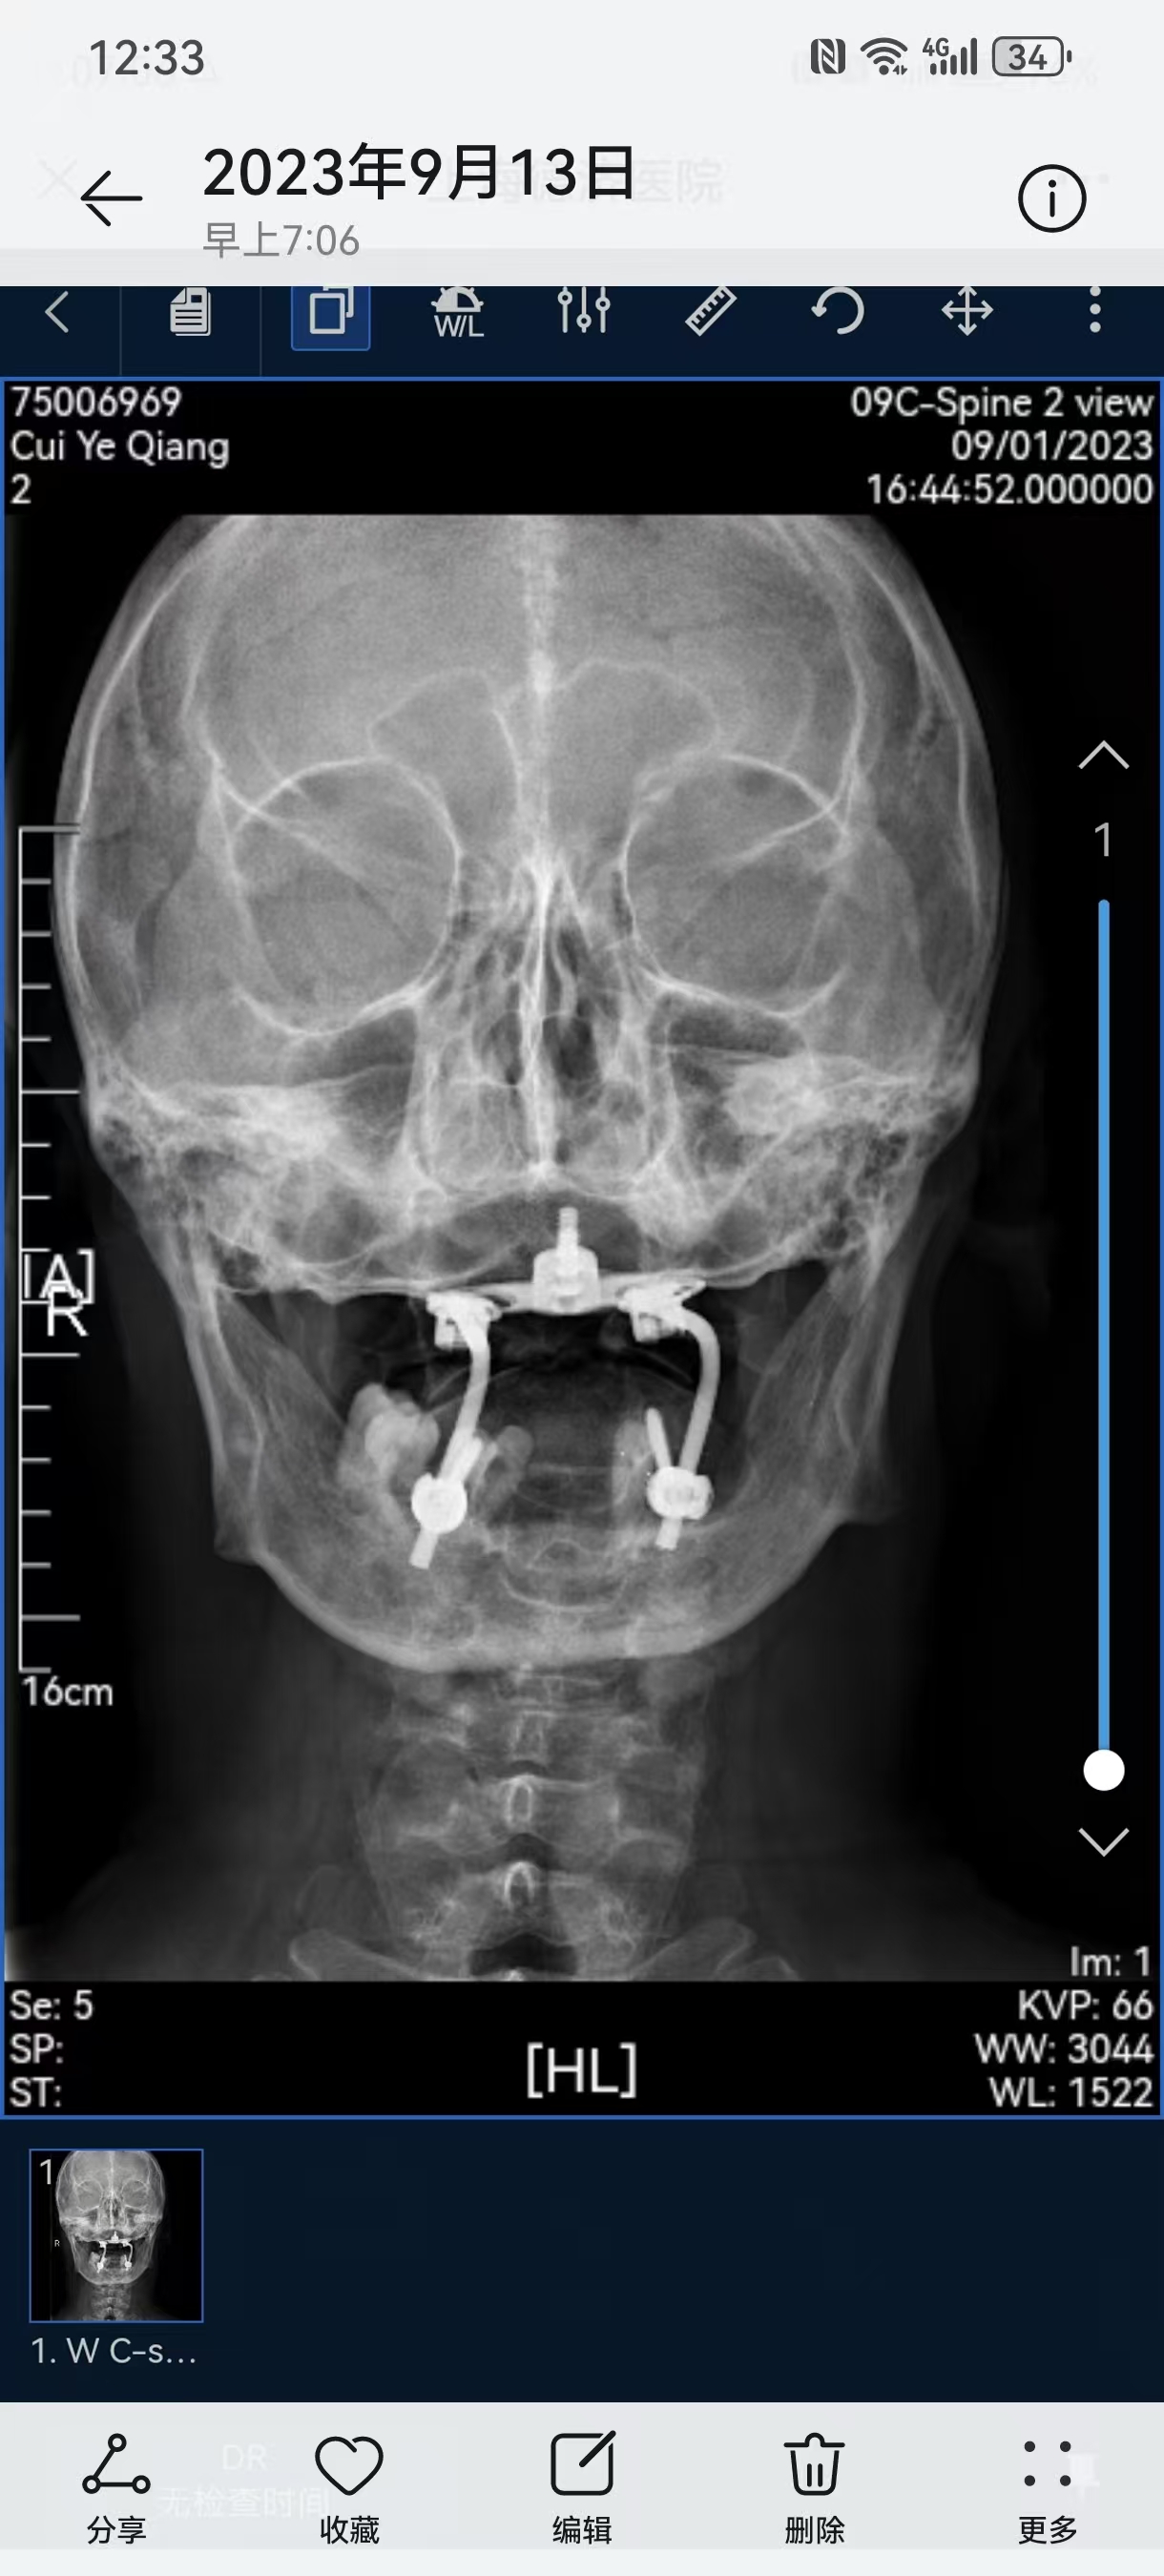

• 诊断:寰枢椎脱位,颅底凹陷

• 2023.09.01,复查,压迫脊髓。